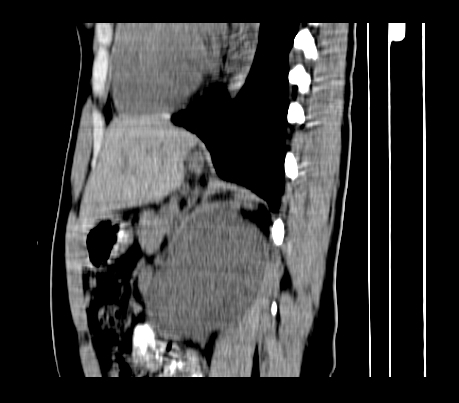

延时5分钟

延时10分钟

重建